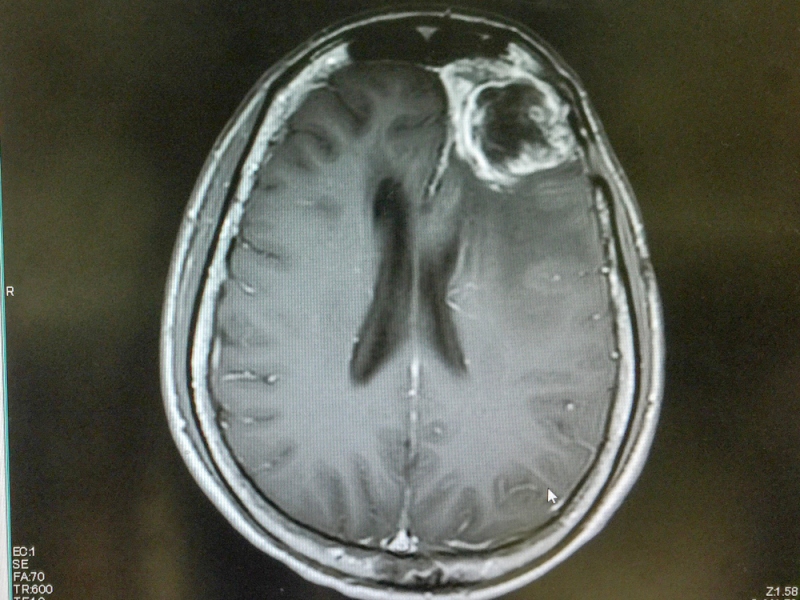

- MRI / CT scan provides a doctor with direct image of the brain tumor and surrounding tissues. Location, size and extent of the glioblastoma spreading become visible.